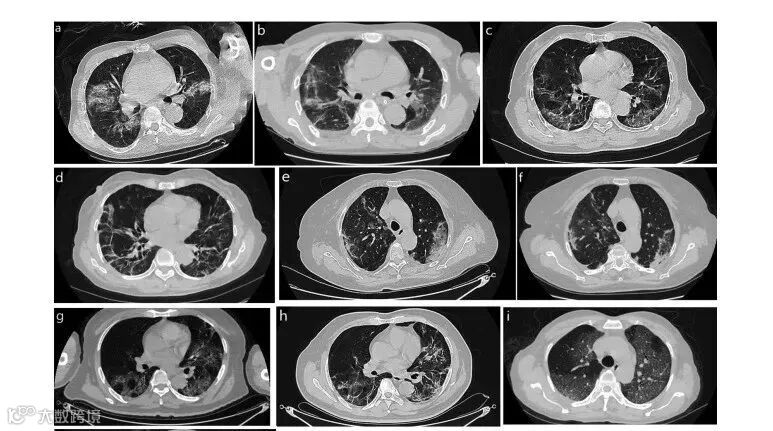

结果显示:脐带间充质干细胞给药对新冠肺炎患者肺部病变和症状的恢复具有长期益处,且患者症状更轻和生活质量更好,睡眠困难、日常活动和NRS评分均得到显著改善。

UC-MSCs对重症COVID-19患者肺损伤的影响